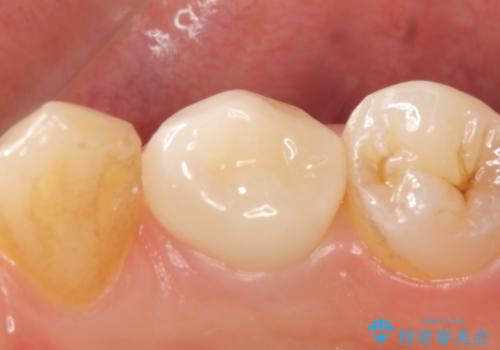

オールセラミッククラウン 咬むと痛む歯の根管治療~補綴

- 右下4番目の歯でものを咬むと疼くような痛みがあるといらっしゃった方の症例です。

X線上で根尖病変を認めたため再根管治療を行い、症状改善後、オールセラミッククラウンによる補綴を行いました。

- オールセラミッククラウン(st)…¥100,000、仮歯…¥10,000、ファイバーコア…¥20,000費用は治療当時の料金となります

オールセラミッククラウンについて

今回用いたオールセラミッククラウンはジルコニアフレームという白い素材の上にセラミックを盛っているため、審美性が非常に高いのが特徴です。

また、ジルコニアは人工ダイヤモンドの材料にも使われているほど高い強度を持っており、そのためオールセラミッククラウンは審美性だけでなく、奥歯やブリッジの補綴も可能とするクラウンです。